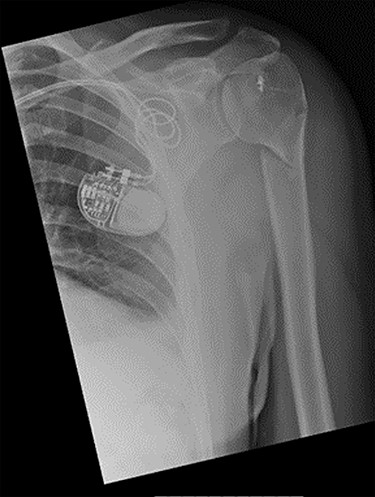

An X-ray of the left shoulder was performed, which revealed acceptable positioning of the fracture. Following a discussion with the patient, a mutual decision was made to manage the injury non-operatively and he was discharged with a collar and cuff sling. Subsequent clinical and radiological review at 1 week and 2 weeks post-injury showed the soft tissues to be healing well and the fracture to be well-positioned (Figs 5 and 6).

Antero-posterior view X-ray taken 1 week post-injury showing acceptable positioning of the fracture.